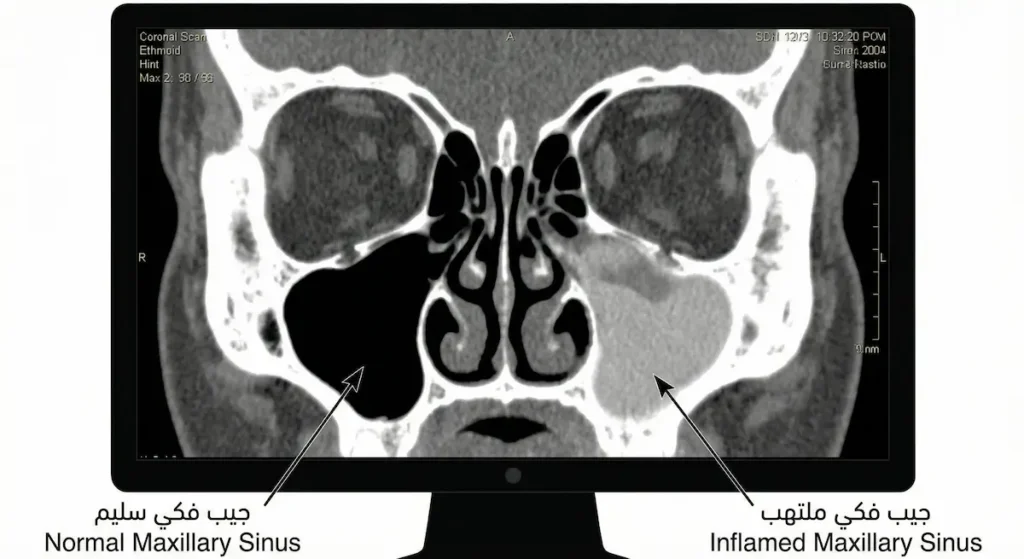

التصوير المقطعي المحوسب (CT Scan) يُعَدُّ المعيار الذهبي لتصوير الجيوب الأنفية. يُظهر بدقة عالية مدى انتشار الالتهاب، وجود سوائل داخل الجيوب، المشاكل التشريحية، والسلائل. لا يُطلب عادةً في البداية بل بعد فشل العلاج الأولي أو قبل التخطيط لعملية جراحية. من جهة ثانية، يُلجأ إلى الرنين المغناطيسي (MRI) في حالات محددة، خصوصاً عند الاشتباه بالتهاب فطري أو ورم، لأنه يُميز الأنسجة الرخوة بشكل أفضل من التصوير المقطعي.